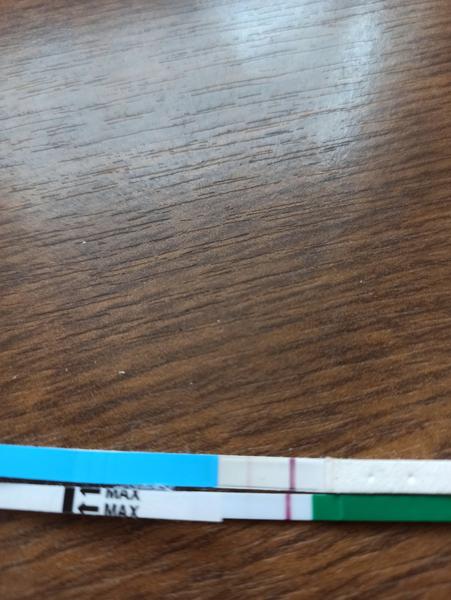

@noemikatka vďaka 🤗noo to je mamatest a keďže nikde som ho nezohnala tak som objednala z internetu,chces stránku?objednalavala som v pondelok poobede a v stredu ráno tu už boli 😊

Baby zaujíma ma či na tomto niečo vidíte,alebo nie,toto je v limite